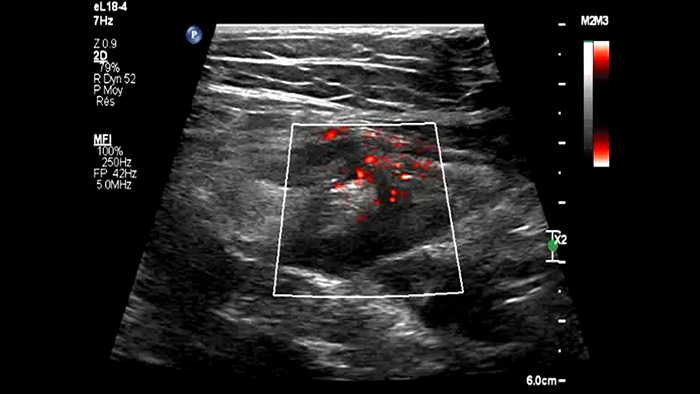

Ces images précises des lésions des couches pariétales forment la base de l’interprétation des changements induits par l’inflammation des parois intestinales et par conséquent de la différenciation entre la maladie de Crohn et la rectocolite hémorragique. L’exploration avec la technologie MFI (MicroFlow Imaging) constitue la deuxième étape. Il s’agit de reconnaître l’aspect de l’hypervascularisation induite par des épisodes inflammatoires actifs. La paroi intestinale normale semble comporter peu de microvaisseaux détectables, uniquement à l’interface de la muqueuse et de la sous-muqueuse, et dans le tissu adipeux mésentérique adjacent. Inversement, la paroi inflammatoire présente de nombreux microvaisseaux. La distinction entre les images d’artefacts de mouvement et les microvaisseaux circulants est alors un point essentiel nécessitant un ajustement parfait des paramètres de détection des micro-flux (voir les boucles, diapositive 8). La comparaison des 4 images suivantes de la maladie de Crohn met en évidence des différences claires qui devraient être interprétées comme étant représentatives des différents états inflammatoires. L’image 1 ne comporte aucun vaisseau visible, ce qui correspond probablement à une absence d’activité. L’image 2 présente quelques vaisseaux ; nous pouvons en conclure que cela correspond à une activité modérée. L’image 3 comporte un plus grand nombre de vaisseaux, signe probable d’une activité intense. L’image 4 présente encore plus de vaisseaux de type pulsatile, ce qui évoque probablement une activité très intense.

Numerous vessels severe activity ?